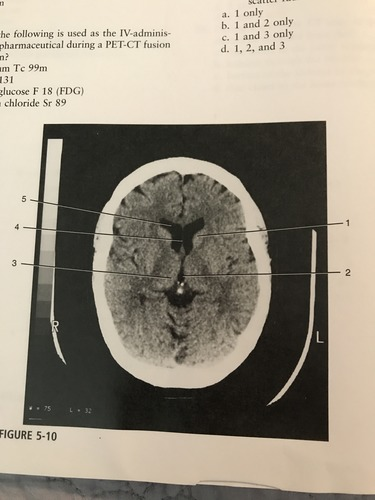

Which number corresponds to the anterior horn of the lateral ventricle

A) 1

B) 5

C) 3

D) 2

Number 3 on the figure corresponds to?

A) caudate nucleus

B) thalamus

C) third ventricle

D) pineal gland

Which number on the figure corresponds to the septum pellucidum?

A) 2

B) 3

C) 4

D) 5

C)4